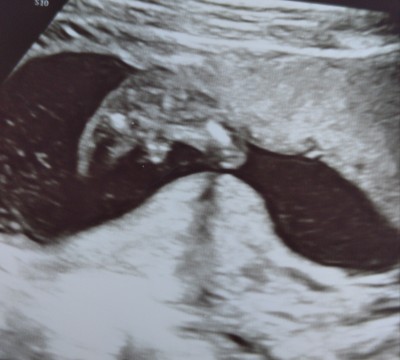

Başak tıpa gittim ordaki doktorda kız dedi bavak arasını net görmesem inanmazdım yinede bi atim sizcede kız dimi :D

image

Böyle de sadece bacak arası fotosu çekti dediğim :))